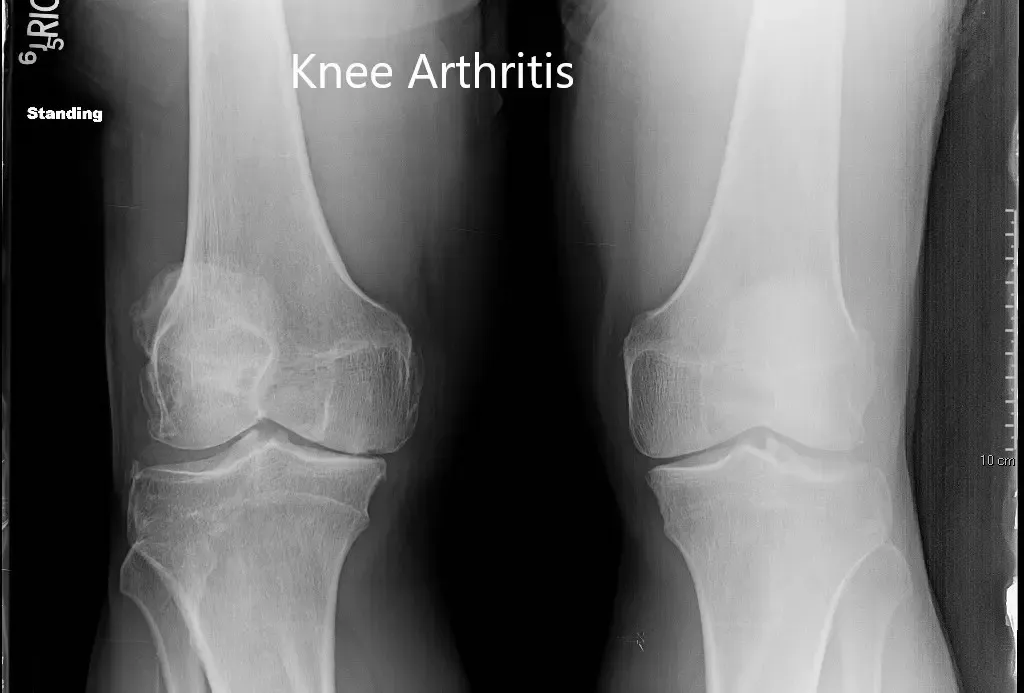

Los estudios de imagen revelaron osteoartritis tricompartmental severa de la rodilla derecha. Teniendo en cuenta el dolor de rodilla que limita el estilo de vida, se le recomendó a la paciente un reemplazo total de rodilla correcto. Todos los riesgos, beneficios y alternativas se discutieron en detalle con el paciente. El paciente aceptó seguir adelante con el procedimiento.

Radiografía preoperatoria de ambas rodillas en vista anteroposterior.